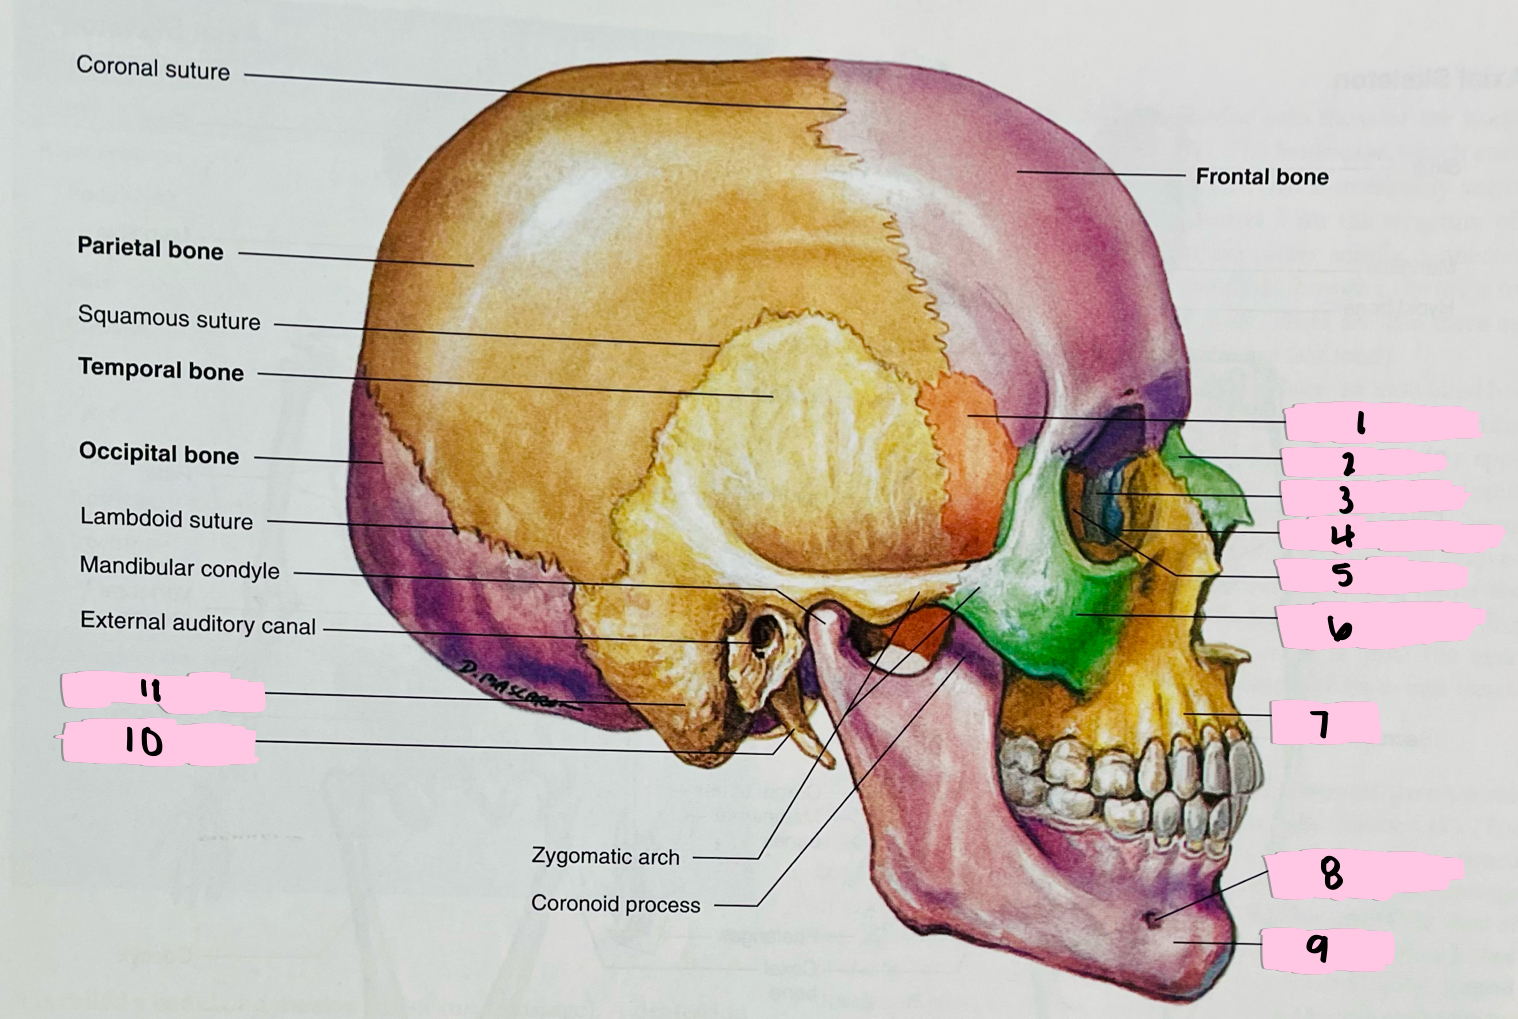

What is 1 pointing to?

Sphenoid bone

What is 2 pointing to?

Nasal bone

What is 3 pointing to?

Lacrimal bone

What is 4 pointing to?

Nasolacrimal canal

What is 5 pointing to?

Ethmoid bone

What is 6 pointing to?

Zygomatic bone

What is 7 pointing to?

Maxilla

What is 8 pointing to?

Mental foramen

What is 9 pointing to?

Mandible

What is 10 pointing to?

Styloid process

What is 11 pointing to?

Mastoid process